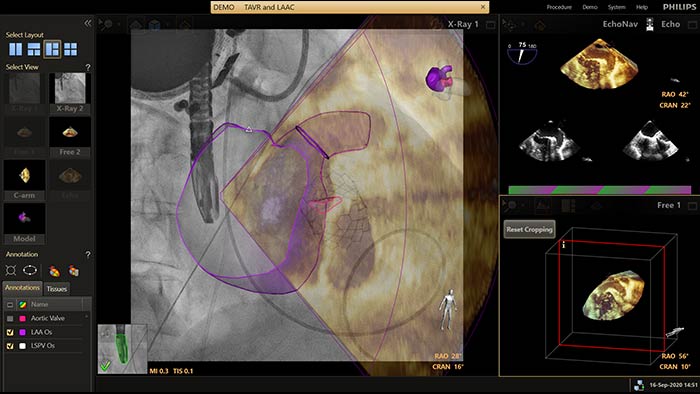

EchoNavigator

EchoNavigator verknüpft Ultraschall- und Röntgendaten auf eine völlig neue Weise in einer erweiterten Darstellung als Führungshilfe und zur Beurteilung der Orientierung von Instrumenten und Gewebestrukturen.

Beim Verschließen des linken Vorhofohrs bietet EchoNavigator folgende Möglichkeiten für höhere Sicherheit und Effizienz:

• Automatische Segmentierung von 3D Utraschalldaten zur patientenindividuellen modellbasierten Darstellung des linken Vorhofes und des Vorhofohrs für verbesserte fluoroskopische Projektionseinstellungen und die Erzeugung eines intuitiveren Navigationskontextes.

• Manuell markierte Landmarken werden vom Ultraschall anatomisch und räumlich korrekt in der Durchleuchtungsprojektion visualisiert. Dadurch lassen sich während der Instrumentenführung in der Durchleuchtung sowohl anatomische Ziele als auch sensible Strukturen, die sonst nicht sichtbar wären berücksichtigen.

• Fusion der Live-Daten von von Durchleuchtung und 3D Ultraschall, ... , zur Darstellung und Validierung der Okkluder Positionierung.